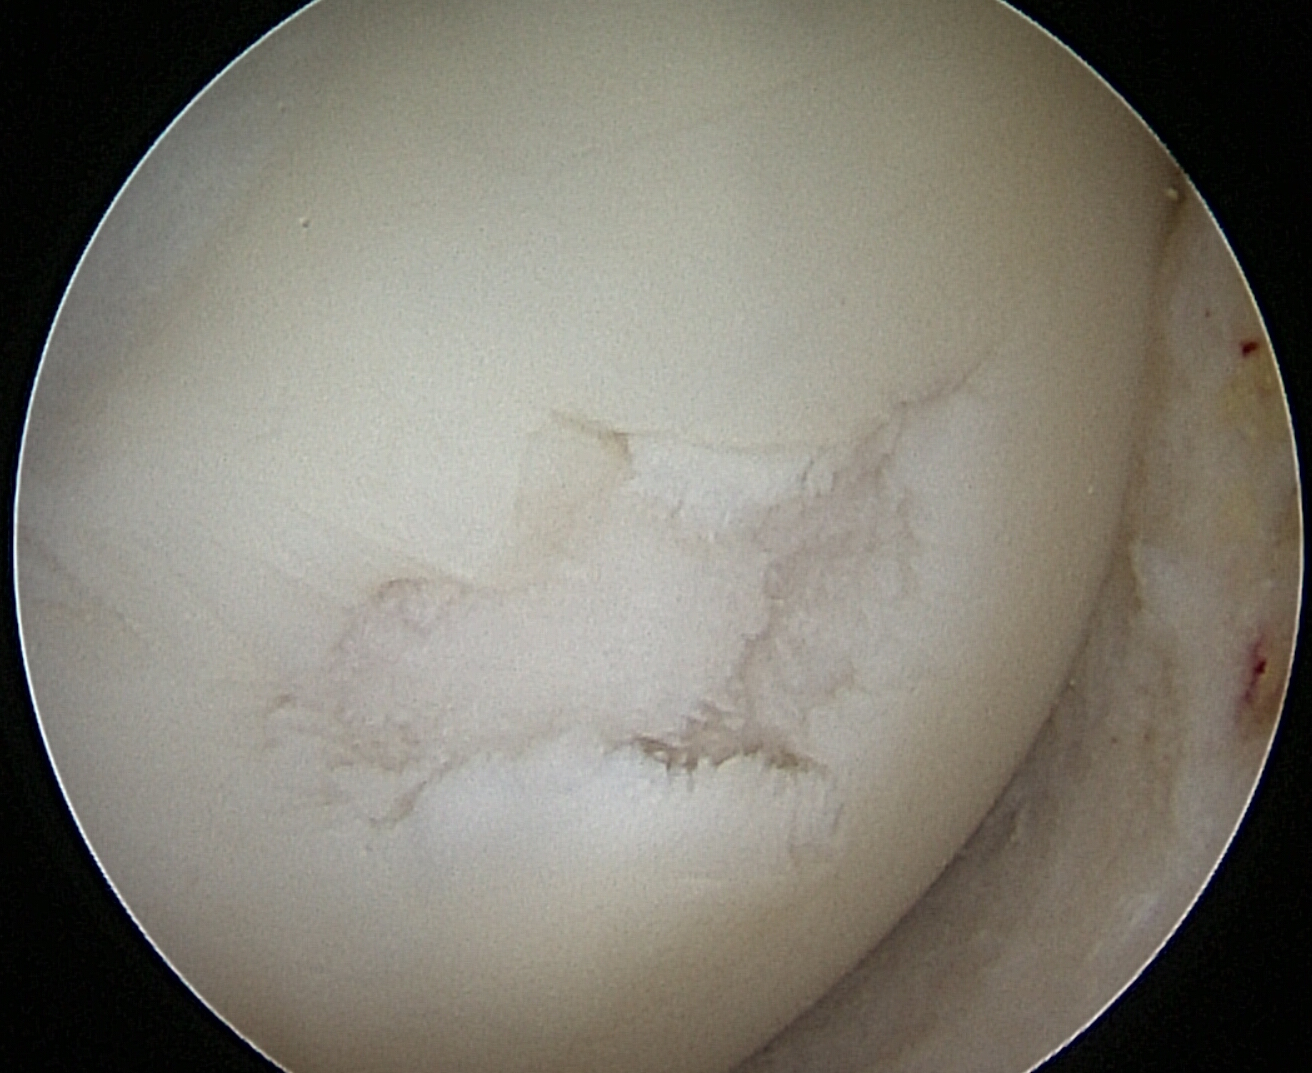

IntroducciónEl trasplante osteocondral autólogo es una alternativa quirúrgica en lesiones focales del cartílago articular. El objetivo de nuestro trabajo fue evaluar una serie de 62 pacientes tratados con mosaicoplastía de rodilla con 8 años promedio de seguimiento.Material y métodosEvaluamos retrospectivamente 62 pacientes operados con mosaicoplastía entre el año 2001 y 2014. Se incluyeron pacientes con lesión de cartílago focal de la rodilla a los que se les realizó mosaicoplastía aislada o asociada a otros procedimientos quirúrgicos (reconstrucción de LCA, osteotomía). Con un seguimiento mínimo de 2 años. Se evaluaron con las escalas de Lysholm e IKDC y el grado de artrosis con la escala radiográfica de Kellgren-Lawrence.ResultadosCuarenta y cinco fueron hombres y 17 mujeres. La edad promedio fue de 36 años. Treinta y cinco en cóndilo interno, 12 cóndilo externo, 12 tróclea y 3 combinadas. Cuarenta y dos fueron mosaicoplastías aisladas y 20 asociados a otro procedimiento. El resultado promedio de la escala de Lysholm al momento de la evaluación fue 80.1 y el IKDC fue 66.7. No encontramos diferencias significativas en la escala de Lysholm e IKDC entre los grupos de mosaicoplastía aislada y asociada a otro procedimiento. En 30 pacientes evaluados con radiografía se observó una inclusión satisfactoria del taco óseo.ConclusionesDentro de las opciones quirúrgicas se encuentran las microfracturas, el auto/alo injerto osteocondral y el implante de condrocitos autólogos. Todas estas técnicas han demostrado mejorar el estado clínico en comparación con el estado preoperatorio independientemente de cuál se utilice. En nuestra serie de pacientes operados con mosaicoplastía encontramos resultados satisfactorios en las evaluaciones clínicas.Consideramos que la mosaicoplastía es un procedimiento con alto grado de satisfacción y buenos resultados funcionales en pacientes con lesiones focales del cartílago articular. AbstractIntroduction: Osteochondral autograft transplantation is a surgical alternative for osteochondral defects of the knee. The aim of this study was to analyze a series of 62 patients treated with osteochondral autograft transplantation of the knee and an average follow-up of 8 years.Methods: A total of 62 patients treated with osteochondral autograft transplantation between 2001 and 2014 were evaluated. Patients with focal osteochondral lesions who underwent osteochondral autograft transplantation alone or associated with another procedure and a minimum follow-up of 2 years were included. Lysholm score, IKDC, and Kellgren- Lawrence radiographic scale were used. Forty-five men and 17 women (average age 36 years) were evaluated. Lesions were localized in medial condyle (35), lateral condyle (12), patella (12), and three were combined. Forty-two patients underwent isolated osteochondral autograft transplantation while 20 patients underwent associated surgical procedures.Results: Mean Lysholm score was 80.1 and IKDC score was 66.7. There were no significant differences in the Lysholm and IKDC scores between groups. Radiographic results demonstrated complete graft incorporation in 30 patients. Clinical evaluation revealed satisfactory results.Conclusion: Osteochondral autograft transplantation to treat osteochondral lesions is a procedure with a high clinical satisfaction and good functional results in patients with focal osteochondral lesions.Descargas